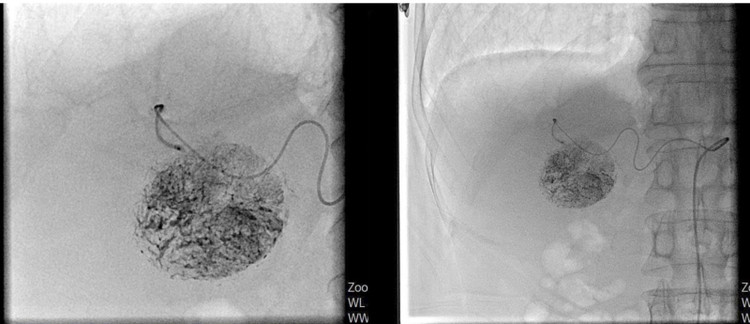

Chúng tôi đã bàn luận với nhau và đưa ra lựa chọn phương pháp TACE – nhẹ nhàng, ít xâm lấn nhưng hiệu quả trong điều trị ung thư gan. Đây là hướng đi an toàn, phù hợp đặc điểm người bệnh”.

Ca can thiệp được tiến hành thành công vào ngày 04/8. Hiện sức khỏe ông C. ổn định, sinh hoạt bình thường, dự kiến xuất viện vào ngày 9/9/2025. Chia sẻ niềm vui, ông nói: “Tôi biết bệnh viện đã có nhiều ca ung thư gan điều trị bằng phương pháp TACE thành công nên rất tin tưởng. Giờ sức khỏe tôi dần hồi phục, cảm ơn bác sĩ đã tận tâm điều trị”.